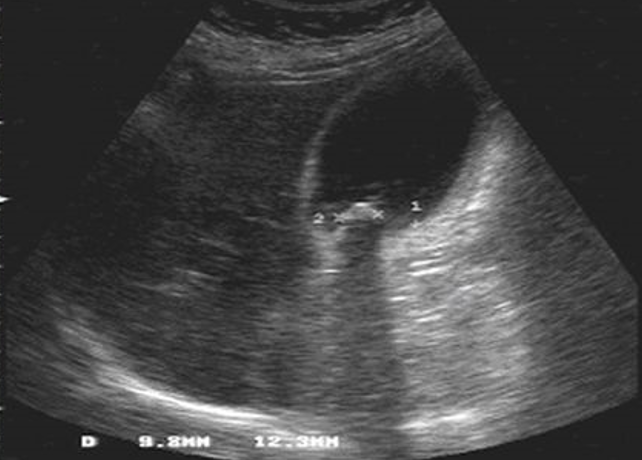

La vesícula biliar es una bolsa de 7 a 10cm de longitud y de 3 a 5 cm de ancho, la cual mantiene en promedio un volumen de 30-50ml; tiene forma piriforme (forma de pera), la cual se divide para su estudio en tres secciones: el fondo, el cuerpo y